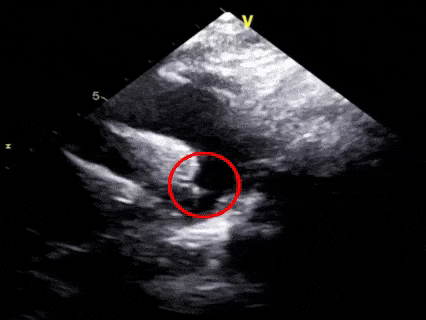

一“贴”,左盘贴壁

超声下可见左盘面展开

后撤整体系统,使左盘面贴靠肺动脉一侧